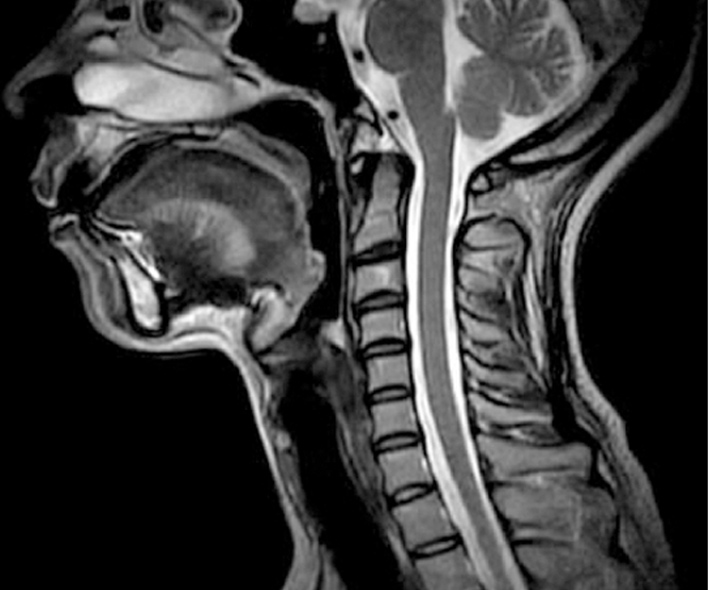

MRIで撮った画像とMRIで分かる疾患の例

頸椎

- 椎間板ヘルニア

- 頸椎症性脊髄症

- 後縦靭帯骨化症 などの症状